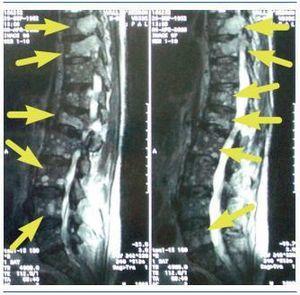

Figura 1.